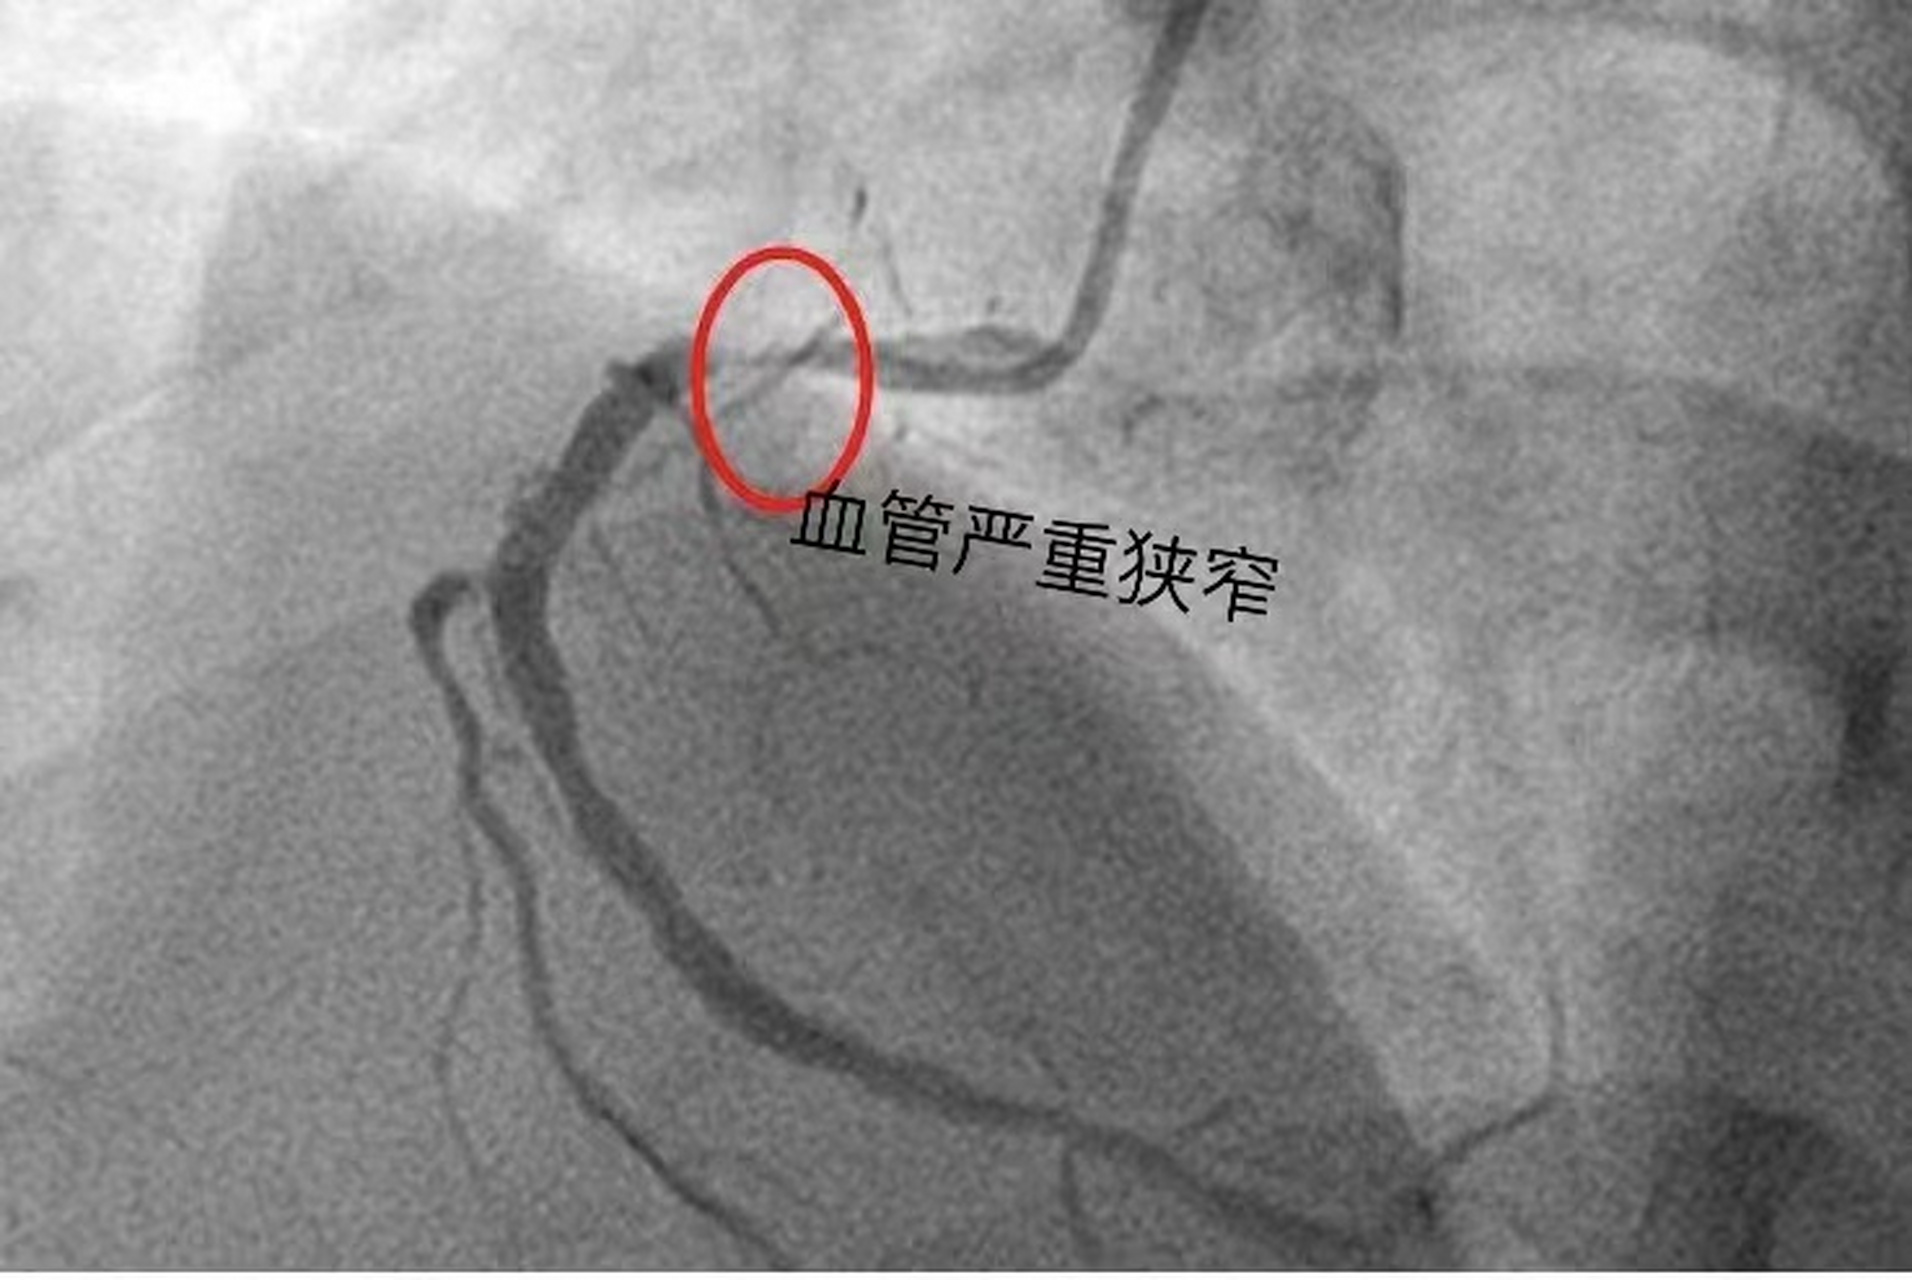

心脏造影,红圈显示近端重度狭窄

术中冠脉造影提示,患者多支动脉血管狭窄病变,前降支次全闭.

做完心脏造影发现,患者有一根血管重度狭窄,差不多有90%的狭窄.